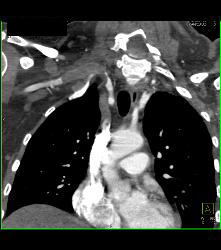

Cervical Rib With Occlusion of the Right Subclavian Artery- See Full Sequence